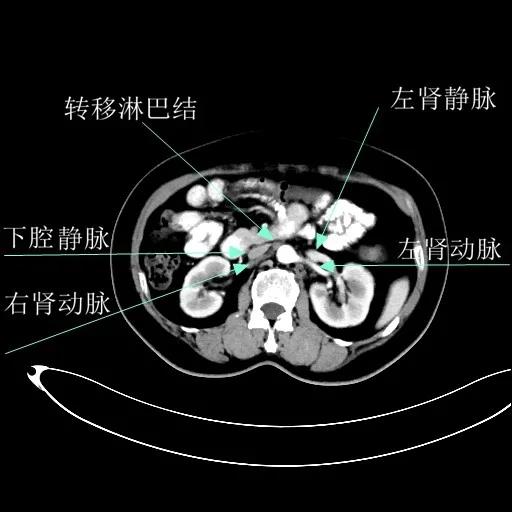

某患者因为“腹痛1周”而入院,外院B超提示子宫上方囊实性肿物,CT提示:左侧附件区占位,并盆腔及腹主动脉旁淋巴结转移。右肾动脉有右肾动脉及异位右肾动脉,其下均有肿大淋巴结。

肾血管总体变异率为35%左右,左侧型发生率为7.5%-23.5%,右侧型发生率为10%-25.3%,双侧型发生率为5.7%。肾动脉一般走行于肾静脉后方。本例异位右肾动脉由腹主动脉发出,经肾静脉前方走行进入右侧肾门,因此称为异位右肾动脉。不论哪个肾动脉分支,均为肾脏相应区域的终末供血动脉,如果发生病变或手术损伤,即可造成相应区域的缺血坏死,因此肾动静脉下淋巴结切除术过程中需警惕异位肾动脉或副肾动脉的存在。

排除禁忌后,在全麻下行“次广泛子宫切除+双附件切除+大网膜切除+阑尾切除术+盆腔淋巴结及腹主动脉旁淋巴结切除术”。术中切除腹主动脉左旁、右旁及后方淋巴结,达左右肾动静脉水平。多个淋巴结呈融合状态,长径约3-5cm。手术由陈亮副主任医师和宋趣清主治医师完成。

术后病理区域淋巴结状态如下:盆腔淋巴结(10/12)见转移;骶前淋巴结(2/2)见转移;腹主动脉左旁淋巴结(13/13)、下腔静脉前淋巴结(6/6)、肾静脉下淋巴结(5/5)、左、右肾动脉下淋巴结(6/6、1/1)见转移。